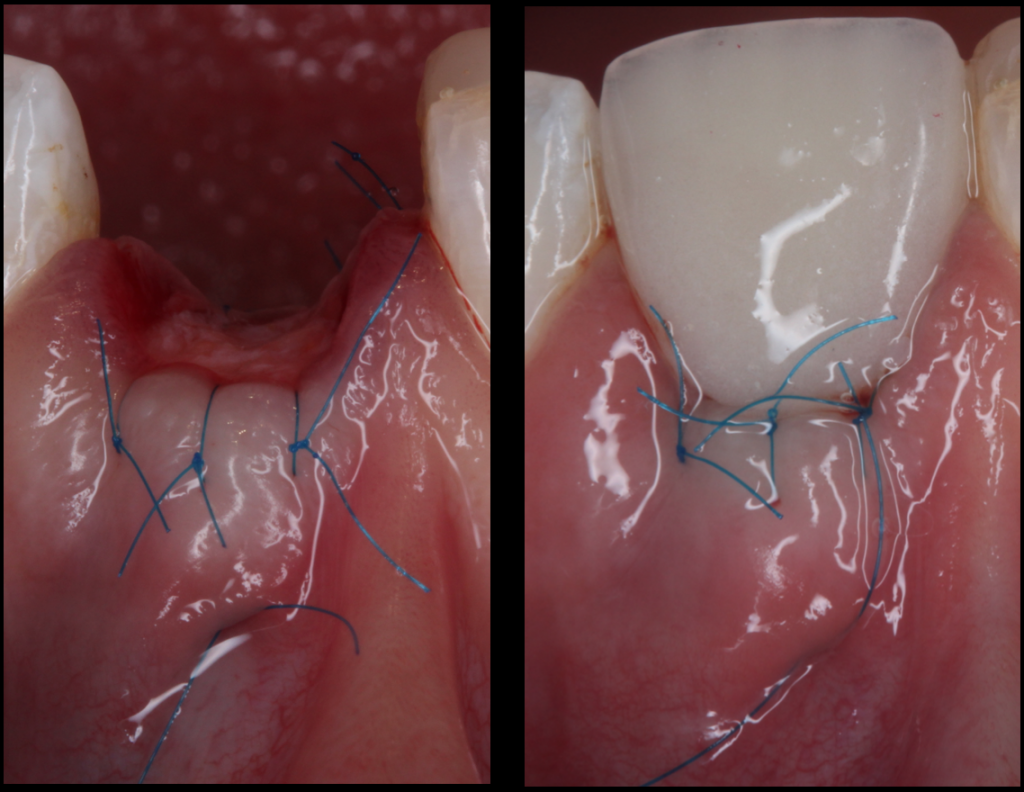

#4. The saddle connective tissue graft

The saddle connective tissue graft associates closure of the extraction site with an increased volume of soft tissues in the buccal part (Chen and Dahlin, 1996).

The graft is positioned in the vestibular and palatal which involves the realization of a buccal supra-periosteal envelope (about 5mm) and a palatal detachment (about 3mm) to introduce the connective graft while preserving the papilla (Fig.5).

The increase in the thickness of the buccal gingiva makes it possible to compensate for the irreversible loss of bone volume despite the filling, and thus to obtain the best horizontal and vertical preservation of the soft tissues (Vanhoutte et al., 2014).

This approach, which is more complex, increases the quantity of soft tissues, particularly in the case of a fine periodontal phenotype, and thus reduces the need for a connective graft during implant placement. Some authors recommend keeping an epithelial area on the exposed part of the graft.